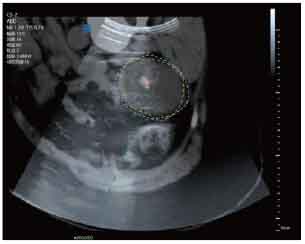

MRI-Ultrasound Fusion in Transperineal Prostate Biopsy

Bi-planar MRI-Ultrasound real-time fusion

3D navigation and tracking

Automatic visualization of lesions and systematic targets